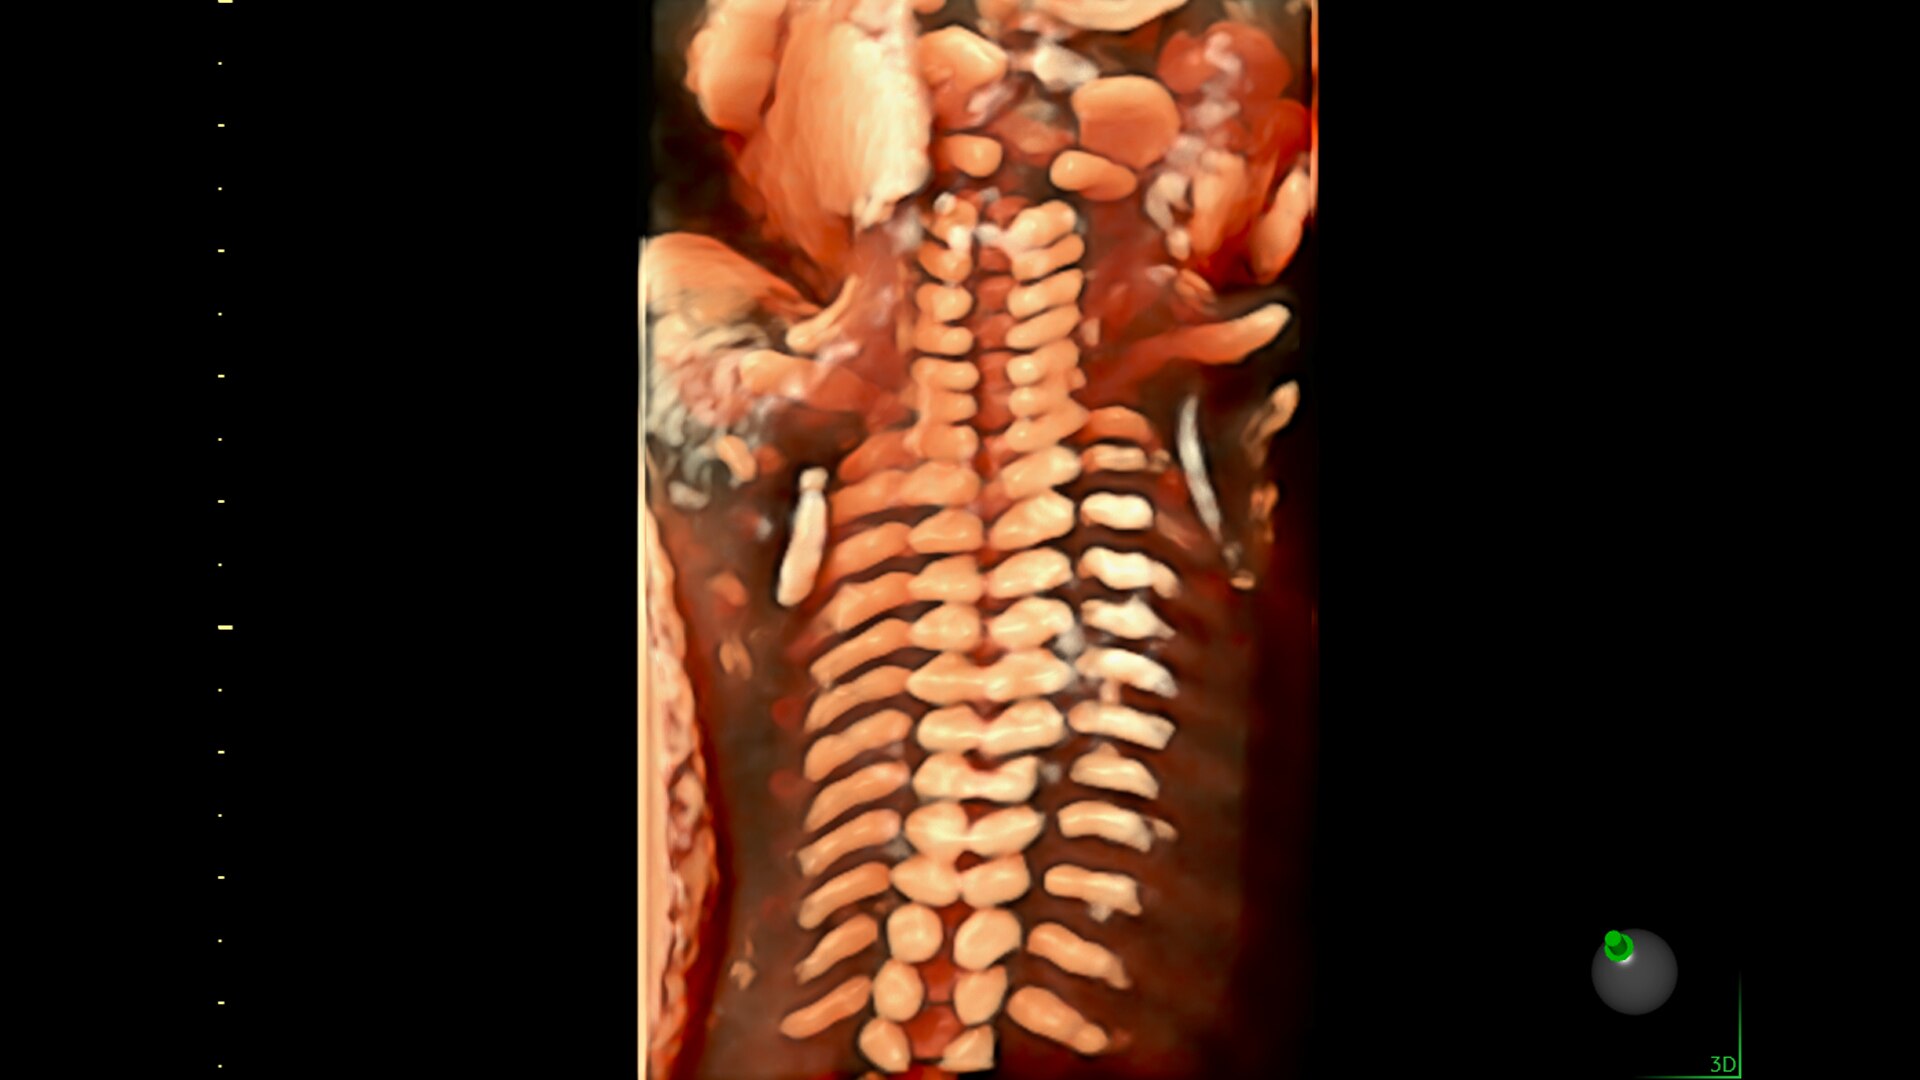

Spine Trace

Welcome to easy 3D in 1/2 the time. Simply trace the spine and the system automatically acquires the volume and displays the coronal view - with 83% less keystrokes.